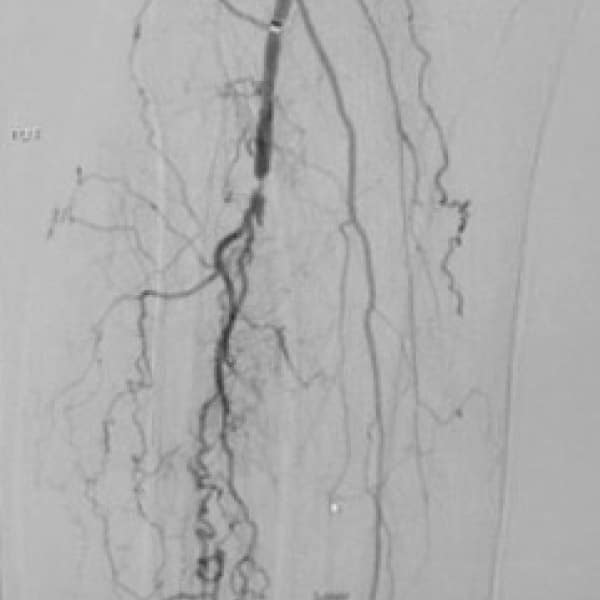

PHYSICIAN: Peter A. Soukas, MD, FACC, FSVM, FSCAI, FACP, RPVI

• Smoker with high blood pressure, hyperlimpidemia

• S/P traversal of left popliteal/TPT occlusion with stent placed in 2017

• Recurrent left calf claudication with duplex confirming occluded stent

• Wingman™ intraluminal crossing; laser PTA and DCB

• CTA of restored distal runoff